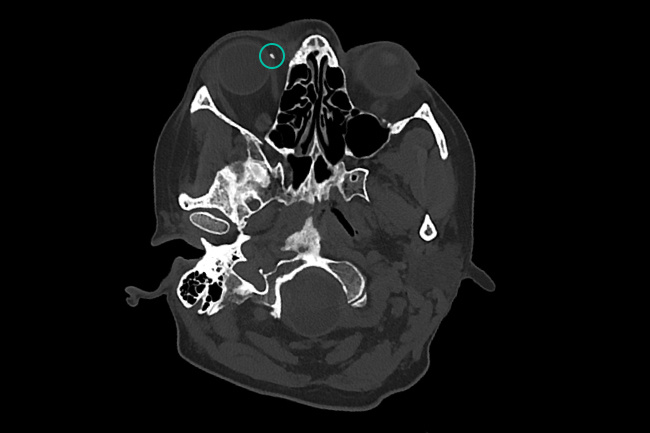

Кальцинат в области глазницы.